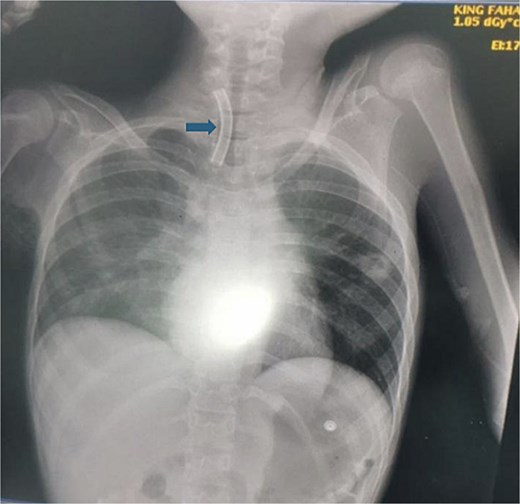

A 10-year-old female patient was diagnosed with cerebral palsy at birth. As her condition progressed, she developed respiratory muscle weakness and was ventilator dependent with tracheostomy for 5 years. While the patient was in the pediatric intensive care unit (PICU), the medical team observed separation of the tracheostomy wing and cannula dislodgement. Upon arrival for 5 min, the patient showed signs of respiratory distress and oxygen saturation was ~80%. The tracheostomy opening was almost closed, and the oxygen saturation continued to decrease. An immediate chest radiograph was obtained to locate the dislodged cannula. The cannula had migrated into the right main bronchus (Fig. 1).

This figure demonstrates the patient chest X-ray showing the radio-opaque cannula in the right main bronchus (arrow).